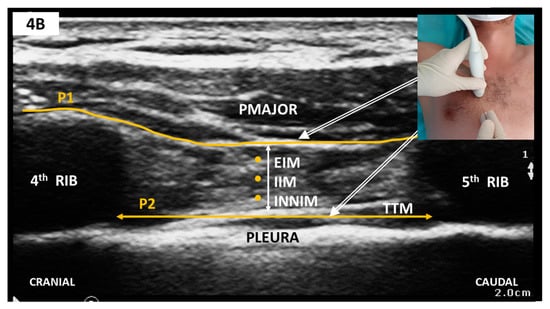

2.3.3. Anteromedial CWFPB—Parasternal Block Variants

Sonoanatomy and Block Technique (Figure 4)